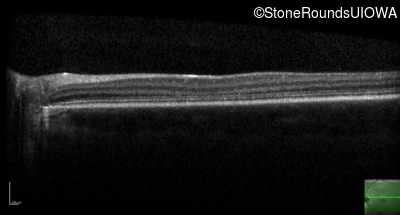

Age at visit: 13 years (Visit 2)

Age at visit: 14 years